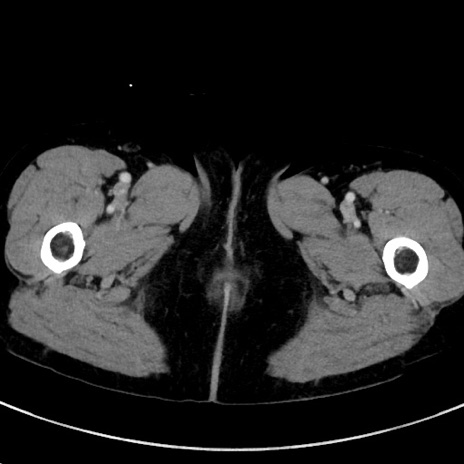

症例23(横断像)

【症例】70歳代女性

【主訴】下腹部痛・嘔吐

【現病歴】2日前より腹痛あり。昨日嘔吐あり。症状改善しないため来院。

【既往歴】胃GISTに対して胃部分切除後。

【身体所見】BT 37.1℃、BP 128/77mmHg、腹部:平坦・軟、下腹部に圧痛あり。

【データ】WBC 10200、CRP 0.31